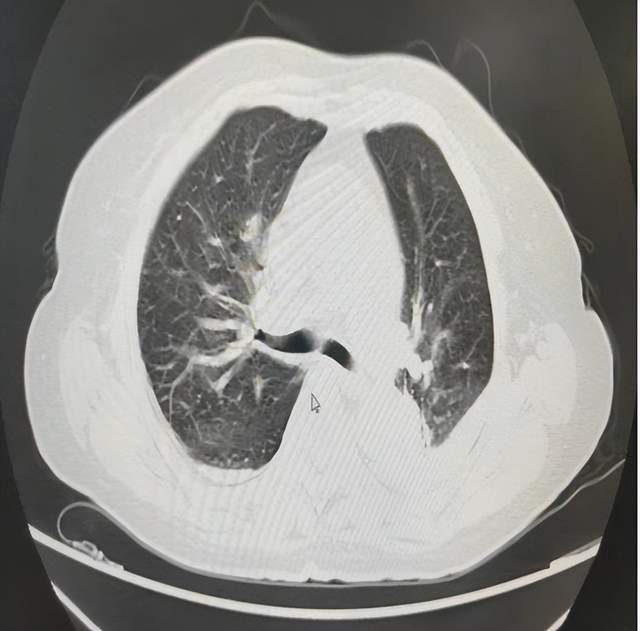

令人头痛的是,通过查看当地医院发来的胸部CT,患者左肺已经完全被血“淹没”,只有右侧肺在维持呼吸。在当地医院两次支气管镜下取血栓,均因活动性出血被迫终止。

患者左肺全肺不张